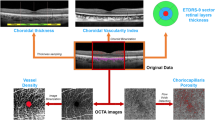

The study was designed as an observational, prospective case series, including RP patients and healthy controls. Multimodal imaging included fundus autofluorescence (FAF), structural optical coherence tomography (OCT), OCT angiography (OCTA) and microperimetry (MP). The follow-up lasted 12 months. For each imaging modality, we performed an overall quantitative analysis and a detailed investigation based on the ETDRS-9 sectors grid. Quantitative parameters included the thickness of each retinal and choroidal layer, vessel density (VD), choriocapillaris porosity (CCP), FAF intensity and MP retinal sensitivity.

The ophthalmologic examination included best-corrected visual acuity (BCVA) measurement, using the standard Early Treatment Diabetic Retinopathy Study (ETDRS) chart, anterior and posterior segment slit-lamp evaluation, and Goldmann applanation tonometry. The quantitative assessment of FAF intensity, and structural OCT, OCTA and MP images included an overall analysis and a detailed investigation performed through an ETDRS-9 sectors grid (central, inner nasal, inner superior, inner temporal, inner inferior, outer nasal, outer superior, outer temporal, and outer inferior).

Structural OCT images were acquired by means of a spectral-domain OCT instrument (Spectralis HRA2 + OCT, Heidelberg Engineering; Heidelberg, Germany). We included only high-quality images (ART > 25) and used the segmentation tool included in Heidelberg HEYEX device to measure the thickness of all retinal layers automatically on an ETDRS-9 sectors grid (central, inner nasal, inner superior, inner temporal, inner inferior, outer nasal, outer superior, outer temporal, and outer inferior). The tool was used under the supervision of two expert ophthalmologists (AA, EA), producing an ETDRS thickness map for the following layers: central macular thickness (CMT), retinal thickness (RT), retinal nerve fibre layer (RNFL), ganglion cell layer (GCL), inner plexiform layer (IPL), inner nuclear layer (INL), outer plexiform layer (OPL), outer nuclear layer (ONL), and ellipsoid zone thickness (EZ). In addition, the same graders performed the measures of choroidal thickness (CT), Haller layer thickness (HLT) and Sattler layer thickness (SLT). CT and HLT were obtained from a horizontal structural OCT scan centred on the fovea, calculating the mean value of five samples (subfoveal, 750 µm and 1500 µm nasal and temporal). SLT value corresponded to the result of (CT-HLT).

OCTA analysis

OCTA acquisitions included 4.5 × 4.5 mm and 12 × 12 mm foveal scans, with Topcon quality index >70 (Swept source DRI Triton Topcon, Topcon inc., Japan). We obtained the automatic segmentations of superficial capillary plexus (SCP), deep capillary plexus (DCP) and choriocapillaris (CC); all the reconstructions were carefully checked by two experts and manually modified if necessary (AA, EA). All the images were loaded in the ImageJ software package and in-house scripts were used to calculate vessel density (VD) [15], understood as the ratio between white and black pixels of the binarized OCTA images, with the subtraction of the foveal avascular zone area. We adopted a mean threshold to binarize all the images [16], choosing to calculate VD on 4.5 × 4.5 mm scans so as to achieve the best compromise between the field of view and the resolution of the images. We also calculated the CC porosity (CCP) parameter as a measure of the flow voids in the CC, taking as our starting point binarized OCTA CC reconstructions and employing the porosity pipeline included in ImageJ to measure the CCP percentage [17].

FAF and MP analyses

Blue-light FAF images were obtained by the same Spectralis HRA2 + OCT device (Heidelberg Engineering; Heidelberg, Germany). We developed an in-house tool to perform FAF intensity quantification based on the same ETDRS-9 sectors grid. A preliminary step was the normalization of all FAF images to obtain similar grayscale distribution. We then centred the ETDRS-9 sectors grid on the fovea and the algorithm provided the global FAF intensity within the grid and the values for each sector.

MP (MAIA, CenterVue, Padova, Italy) was carried out employing the 4–2 threshold strategy, with a 68-stimuli grid covering the central 10° of the retina, manually centred on the fovea by two experts (AP, LB) [18, 19]. In this case, we once again adopted an in-house tool to perform an ETDRS-9 sectors grid-based analysis of retinal sensitivity, including global and sector values.

The complete ETDRS analysis is shown in Supplementary Table 1, while the merged thickness analysis of inner and outer grids is shown in Table 3. Looking at the global values, RNFL, GCL, IPL, ONL and EZ were found to be significantly thinner in RP than in controls (p < 0.05), whereas INL and OPL were significantly thicker in RP eyes (p < 0.05). At the same time, FAF intensity and MP retinal sensitivity were significantly lower in RP than in control eyes (p < 0.05). A separate analysis of the inner rings confirmed these findings (all p < 0.05), the only exception being RNFL, which largely matched healthy values (p > 0.05). In contrast, looking at the outer ring values, we find that all the global findings were confirmed (all p < 0.05) except for INL values, which proved analogous to those of healthy controls (p > 0.05). We detected no significant changes in all the parameters after one year of follow-up (all p > 0.05). The distribution of retinal layer thickness changes occurring in RP is plotted in Fig. 1. The detailed description for each layer is provided in the figure legend. Overall, all ETDRS sectors displayed considerable changes in retinal thickness and MP retinal sensitivity values; it is worth noting the evident alterations detected in sector S1 with regard to IPL thinning, INL and OPL thickening, and MP values (Fig. 1). RP eyes exhibited diffuse reductions in the FAF intensity pattern affecting both inner and outer sectors. Remarkably, an evident FAF intensity reduction was detected in the central sector (Fig. 1 and Supplementary Table 1).

For each plot, healthy controls are shown in blue, RP values at baseline are shown in orange and RP values at 1-year follow-up are shown in grey. In RNFL the most extensive thinning occurs in S2, N2 and I2. Conversely, GCL is distinguished by diffuse thinning involving all the ETDRS grid sectors, the most pronounced being S1, S2, I1 and I2, with C being the only exception. IPL shows a diffuse thinning in S1, N1, I1, T1 and T2, whereas it is found to be thicker in C. Conversely, INL proves thicker overall in C, S1, N1, I1, T1, I2 and T2, whereas OPL turns out to be thicker in C, S1, S2, N2, I2 and T2. In both INL and OPL, the most pronounced changes are detected in S1. ONL and EZ prove to be thin throughout in RP. As regards MP retinal sensitivity, the lowest values are detected in the outer ring sectors. Interestingly, the most extensively affected inner sector is S1, while the others share similar MP values. Lastly, FAF displays reduced diffuse intensity, affecting both inner and outer sectors, and this reduction is curiously particularly marked in the C sector.